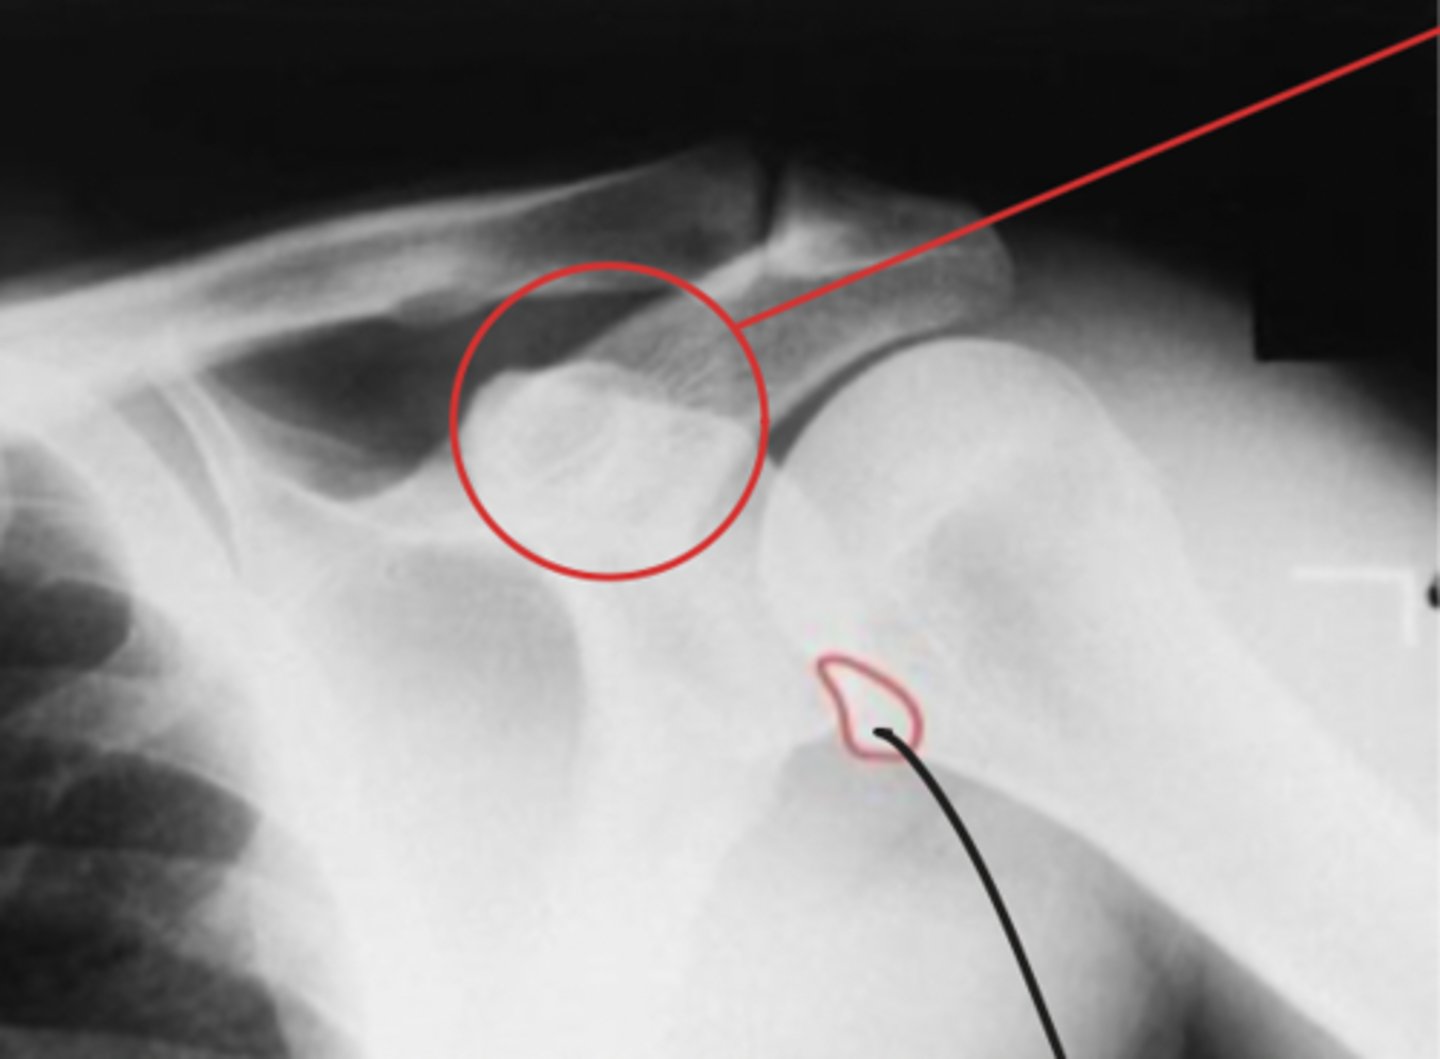

Posterior dislocation of GHJ

What is the issue?

Hill Sachs lesion

Bankart fracture